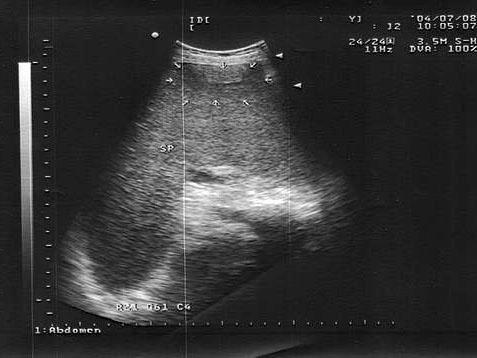

男,18岁,外伤1小时就诊。结合超声声像图,诊断为?(?)A.脾外伤血肿B.脾淋巴管瘤C.膈下积液D.脾皮样囊肿E.脾血管瘤

问题 男,18岁,外伤1小时就诊。结合超声声像图,诊断为?(?)

选项 A.脾外伤血肿 B.脾淋巴管瘤 C.膈下积液 D.脾皮样囊肿 E.脾血管瘤

答案 A